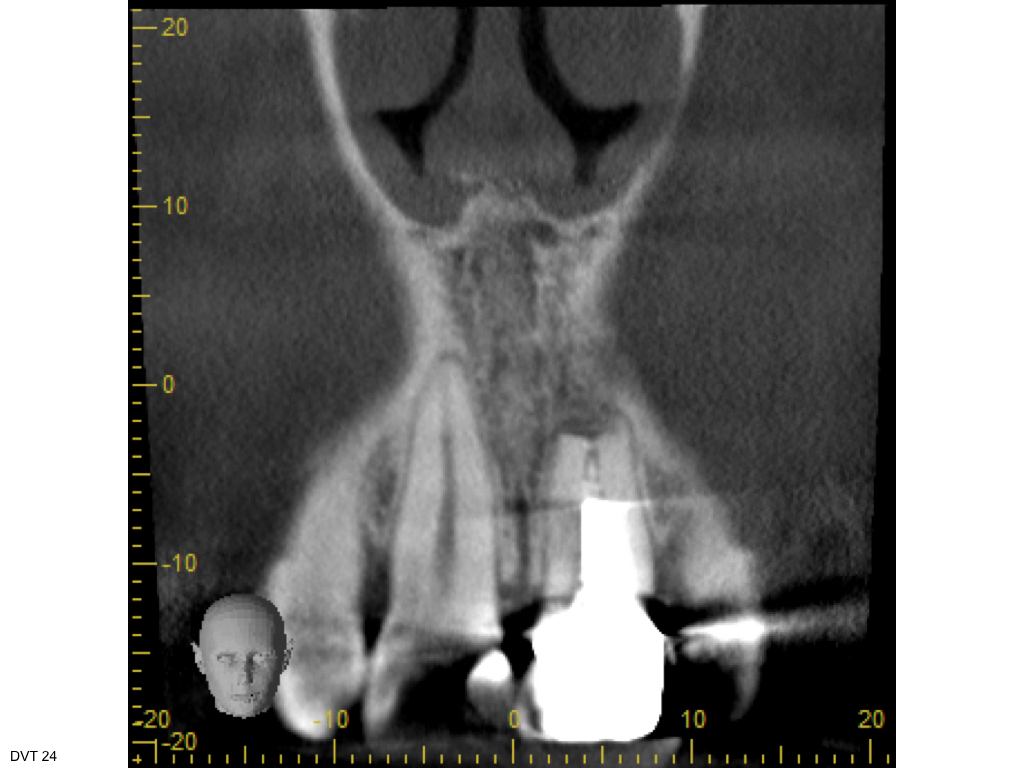

WS 04082016.003 Veröffentlicht 2. August 2016 am 1024 × 768 in Zustand nach traumatischer Zahnverletzung mit nachfolgender Wurzelbehandlung und Wurzelspitzenresektion